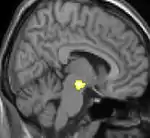

|  |  |  |

| La tomographie par émission de positons (TEP) montre les zones du cerveau étant activées durant la douleur | ||

| La morphométrie voxel par voxel (VBM) montre les différences structurelles des zones du cerveau | ||

Les images par tomographie à émission de positron indiquent les régions du cerveau qui sont activées lors de la douleur, par rapport aux périodes sans douleur. Elles montrent les régions du cerveau qui sont toujours actives durant la douleur en jaune/orange (appelé "matrice-douleur"). La zone au centre (dans les trois vues) est spécifiquement activée uniquement pendant la crise. Les photos sur la ligne du bas (effectuées par VBM) montrent les différences structurelles entre les patients souffrant d'AVF et des personnes saines : seulement une partie de l'hypothalamus est différente[50],[51].